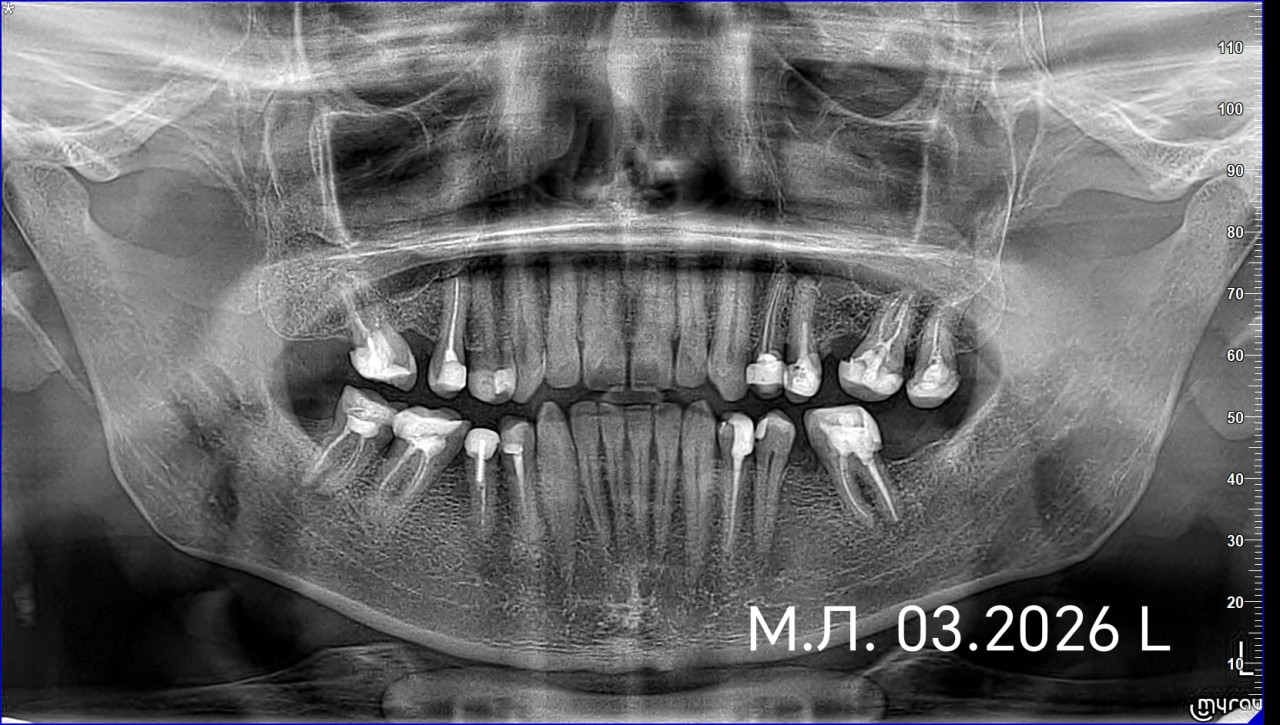

Хочу поставить коронки на зубы, т.к. много жевательных зубов с большими пломбами. Имеются панорамный снимок, отдельные снимки зубов. Какой план лечения перед установкой циркониевых коронок?

Здравствуйте. По снимкам видно несколько зубов с большими пломбами и ранее пролеченными корневыми каналами, поэтому перед установкой циркониевых коронок обычно проводится санация полости рта: лечение кариеса, оценка и при необходимости перелечивание каналов, профессиональная чистка, удаление безнадёжных зубов, затем восстановление культей и только после этого подготовка зубов и фиксация коронок. Окончательный план лечения составляется после очного осмотра и оценки каждого зуба отдельно.